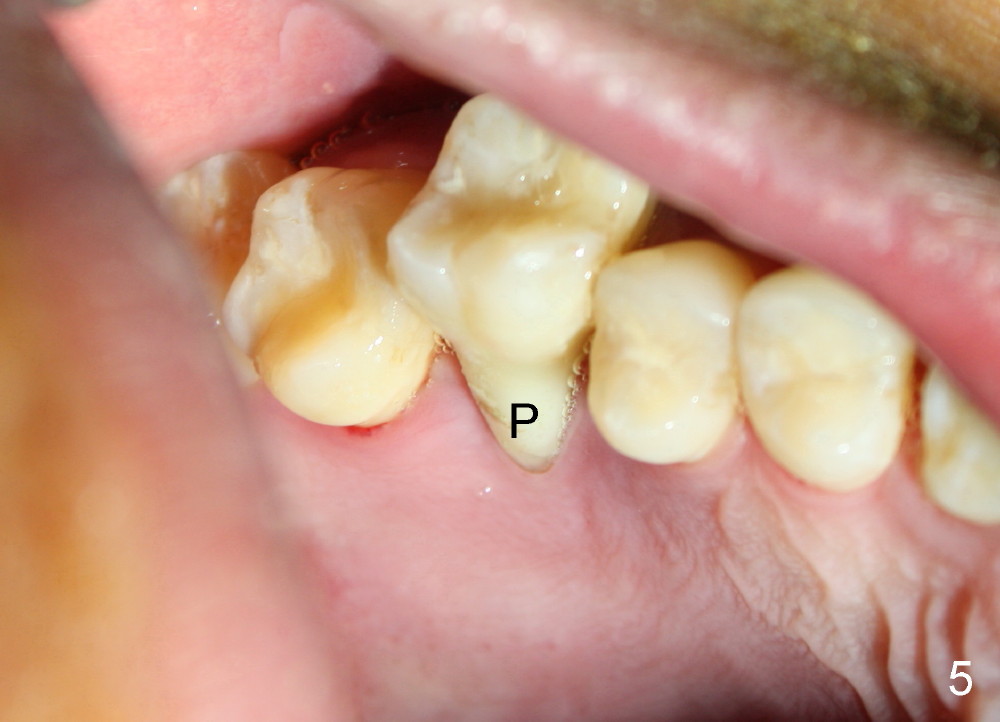

The tooth #3 has severe periodontitis with probably endodontic lesion (Fig.1,2). The patient is a 43-year-old man with apprehension of dentistry. An acute infection causes pain and tooth shift (Fig.4,5). A 7x17 mm immediate implant is planned (Fig.3). The palatal socket is shallow (Fig.6 P), corresponding to severe recessive palatal root (Fig.5 P). The osteotomy is created mainly in the buccal socket (Fig.6 B), exactly in the lingual slope of the septum. Initially osteotomes are used, followed by tap placement (Fig.7 T (4.5x20 mm at the depth of 17 mm). When the implant is placed as planned (Fig.8 I), there is more vertical contact (Fig.8 red line) than that associated with the tap (Fig.7 red line). The corresponding insertion torque is between 50 and 60 Ncm. There is only one small gap buccally, which is filled with bone graft (Fig.9 <). After the insertion of a short abutments with vertical slots (Fig.9,10 A), perio dressing is used to cover the wound. The palatal socket is expected to heal uneventfully (Fig.10 P). In fact, it does in 7 days (Fig.12 P); the bone graft in the mesiobuccal aspect is healing and stabilized (Fig.11 <). By two weeks postop, the mesiobuccal socket has healed (Fig.13 <). With removal of a diseased tooth, our body has amazing power to heal.